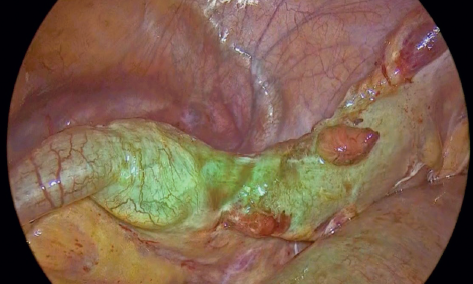

Durante el procedimiento quirúrgico, entre los hallazgos importantes se observaron asas intestinales con dilatación significativa y líquido libre inflamatorio en cavidad. En fosa ilíaca derecha se evidenció zona de conglomeración de asas, por lo que se sospechó que el sitio de la oclusión se encontraba ahí. Se inició disección hasta evidenciar asa de íleon terminal comprimida por presencia de una “adherencia” que colapsaba el paso intestinal; se procedió a disecarla para localizar el origen de la oclusión (figuras 2 y 3).

Durante la disección se evidenció que el colapso del asa de íleon fue provocado por un anillo constrictor apendicular causado por el apéndice cecal. Se continuó con la disección hasta localizar la base y la punta apendicular; esta última se encontraba firmemente adherida al íleon (figura 4). Se realizó disección roma de la punta apendicular, logrando separarla del íleon sin lesión en este. Una vez liberada la porción, se revisaron las características de coloración y se corroboró la perfusión con filtro de verde de indocianina (ICG) (figuras 5 y 6).

Imágenes: Salinas-García et al.

Figura 4 Imagen laparoscópica del apéndice cecal inflamado y su base.